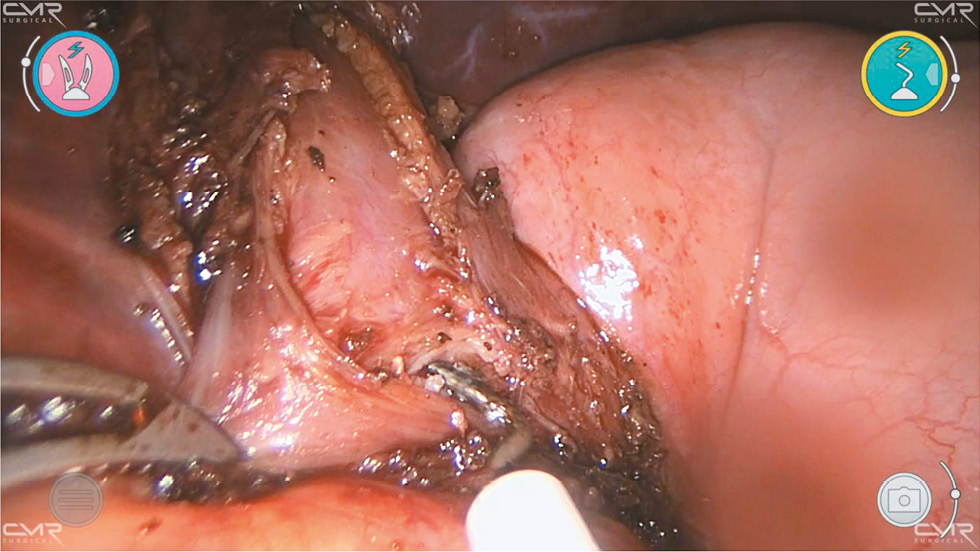

После адекватной миотомии через назогастральный зонд выполняют аэропробу с инсуффляцией воздуха для проверки герметичности слизистой оболочки. Кончик зонда в это время находится в пищеводе над местом хирургического вмешательства. Затем дно желудка перемещают к разрезу пищевода и выполняют частичную переднюю фундопликацию по Дору путём подшивания дна желудка к краям миотомии нитями PDS II 2–0 (рис. 3, рис. 4).

Рис. 4. Роботизированная миотомия Хеллера: этап фундопликации по Дору (фиксация медиального края манжеты).

Fig. 4. Heller robot-assisted myotomy: Dor fundoplication stage (fixation of the medial edge of the cuff).